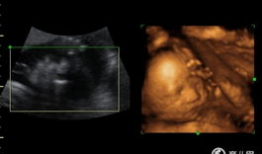

四维视频,四维视频揭秘未知世界

哇,你有没有想过,未来看电影会是什么样子?想象你戴上眼镜,眼前不再是平面的画面,而是一个立体的世界,仿佛你真的置身其中。这就是四...